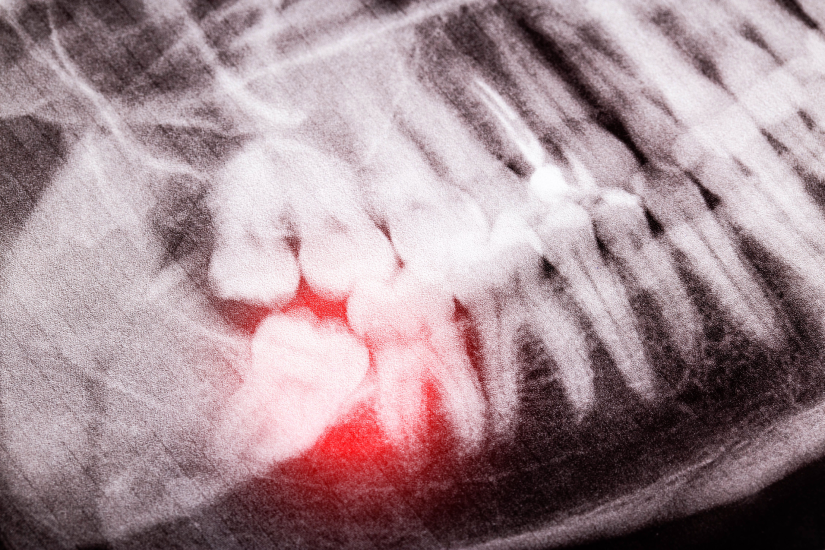

Diagnosticul de precizie: cum se identifică incluzia?

Diagnosticul incluziei dentare se bazează pe examinarea clinică și, esențial, pe investigații imagistice. Medicul stomatolog va observa absența unui dinte pe arcadă sau semne de inflamație și va recomanda radiografii pentru a confirma.

Investigațiile imagistice sunt cruciale nu doar pentru a confirma prezența dintelui inclus, ci și pentru a-i evalua exact poziția și relația cu structurile anatomice vecine (alți dinți, nervi, sinusul maxilar). Iată care sunt:

- Radiografia panoramică (OPG): Oferă o imagine de ansamblu a ambelor maxilare și este adesea primul pas în diagnosticarea dinților incluși, în special a molarilor de minte.

- CBCT (Tomografia computerizată cu fascicul conic): Aceasta este investigația de elecție pentru cazurile complexe. CBCT-ul oferă o imagine 3D extrem de detaliată, permițând medicului să vadă exact poziția dintelui din toate unghiurile, relația cu rădăcinile dinților vecini și cu nervul alveolar inferior (în cazul molarilor de minte).